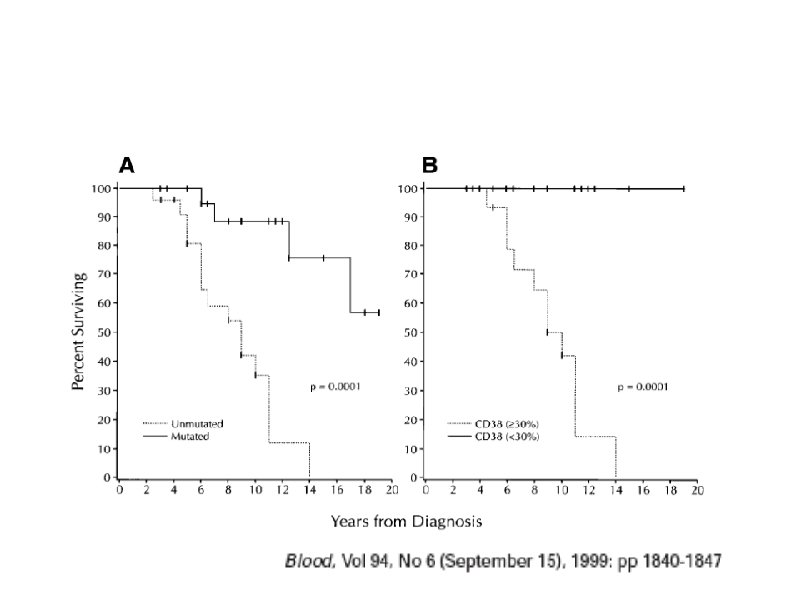

Время удвоения лимфоцитов менее 6 месяцев Время удвоения лимфоцитов более 6 месяцев Стадия на момент диагноза III – IV / C (Rai / Binnet) Возраст менее 65 лет I – II / A Возраст более 65 лет ZAP-70 < 20% Соматическая мутация (-) Соматическая мутация (+) 17 p делеция (p 53 мутация), 13 q делеция 11 q делеция, 12 q трисомия CD 38 (+) CD 38 (-)